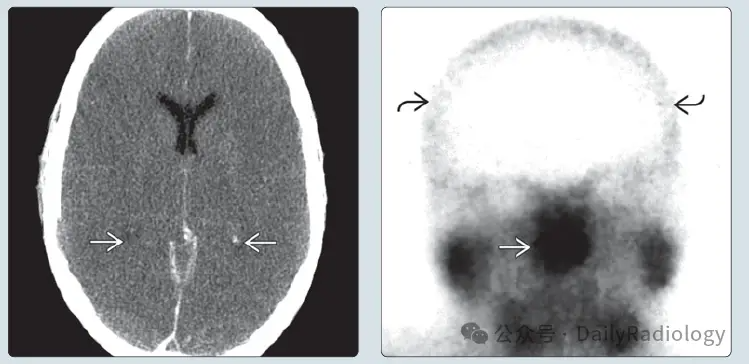

【神经影像】脑死亡的影像表现

- 大面积脑梗死/水肿

病理机制

严重细胞肿胀 → 颅内压(ICP)显著升高